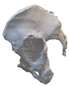

A 3D pelvis reconstruction allowed further processing using the Mimics Innovation Suite (Materialize NV, Leuven, Belgium), which is an engineering software package that enables 3D medical imaging and surgical-related planning. So, the design of the patient-specific aiming device was based on a 3D reconstruction of the patient’s own anatomy. After importing and transforming the two-dimensional Digital Imaging and Communications in Medicine (DICOM) standard file, the radiation absorption range was selected using the windowing method for spatial imaging of the reliable bone structure (Figure 1).

Figure 1.

3D images of the mask that appeared when the CT scans were threshold and the spatial model derived from it. The heads of the implanted screws are displayed in purple.

The default threshold window ranges from 200 to 2000 HU according to the Hounsfield scale, modified to consider the parameterization of the recordings and the specific density of the selected bones.

The selected range is immediately displayed on the screen so that the consequence of the change in the threshold values can be immediately evaluated on the CT slice images in the form of a colored highlight.

The mask obtained in this way contained only the real bone volume relevant to the task, in our case, the pelvis with significant bone defects and the femur on the same side.

After smoothing the mask to remove surface roughness due to the low resolution of the diagnostic imaging, the hemi-pelvis with significant bone defect was printed using a Stratasys F270 (Stratasys Ltd., Rehovot, Israel) fused deposition modeling (FDM) 3D printer. A square grip was attached at the sacrum in such a way that the model could be exposed on a stand and used as a reference to facilitate the spatial orientation in the OR.